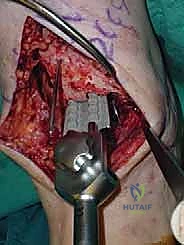

يقوم الدكتور هطيف بعمل شق طولي دقيق في الجزء الأمامي من الكاحل، طوله حوالي 10-15 سم. يتم تشريح الأنسجة بعناية فائقة للوصول إلى المفصل.

* الحماية العصبية الوعائية: هذه هي الخطوة الأكثر حرجاً. يتم تحديد الحزمة الوعائية العصبية (الشريان الظنبوبي الأمامي والعصب الشظوي العميق) وسحبها برفق شديد لحمايتها من أي ضرر جراحي.

3. إزالة النتوءات العظمية وتحضير المفصل (Debridement)

بمجرد كشف المفصل، يقوم الجراح بإزالة الغشاء الزلالي الملتهب والزوائد العظمية (Osteophytes) التي تعيق الحركة. هذه الخطوة ضرورية لاستعادة المعالم التشريحية الطبيعية قبل إجراء القطع العظمي.

4. وضع أدلة القطع (Jig Placement and Alignment)

تعتمد دقة الجراحة على المحاذاة الصحيحة. يتم استخدام أجهزة توجيه متطورة (Jigs) تثبت على عظمة الساق باستخدام دبابيس معدنية. يتم التحقق من صحة الزوايا والمحاور باستخدام جهاز الأشعة السينية المباشر داخل غرفة العمليات (C-arm Fluoroscopy). يضمن الدكتور هطيف أن يكون القطع موازياً للأرض تماماً عند وقوف المريض.